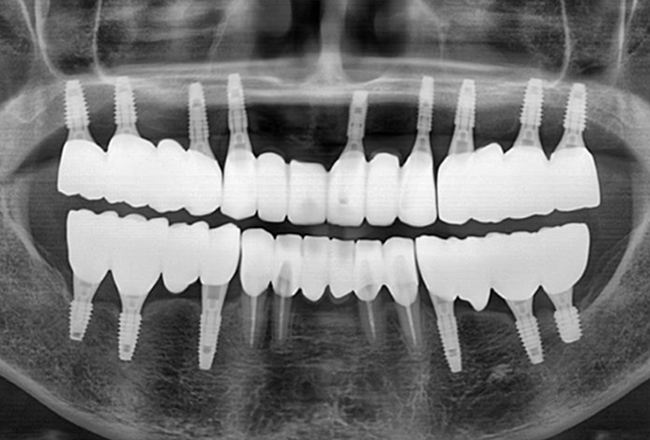

전악 임플란트는 임플란트 틀니보다 씹는 힘이 훨씬 좋습니다.

내 치아처럼 사용이 가능하며

전체 치아 기능의 90% 정도로 회복력이 좋습니다.

개인 치아 형태와 교합을 고려한

최종 보철물을 제작·장착합니다.

자연스러운 사용감과 기능을 확인한 뒤

치료를 마무리합니다.